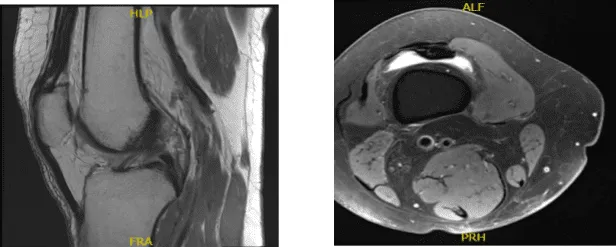

A 68 year-old female patient was seen in the office with right knee pain at Mather hospital and put in a knee brace and referred to us. MRI were reviewed and discussed by the doctor; Complex tear of the medial meniscus.

Mild MCL sprain superimposed on chronic scarring. Moderate chondromalacia patella and mild cartilage loss in the medial compartment. Moderate joint effusion.

MRI Right Knee Non-contrast

Examination of the medial tibiofemoral compartment showed a complex tear of the posterior horn of the medial meniscus along with grade 2 to grade 3 osteoarthritis of the medial femoral condyle.